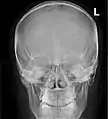

Paranasal sinuses

Paranasal sinuses seen in a frontal view